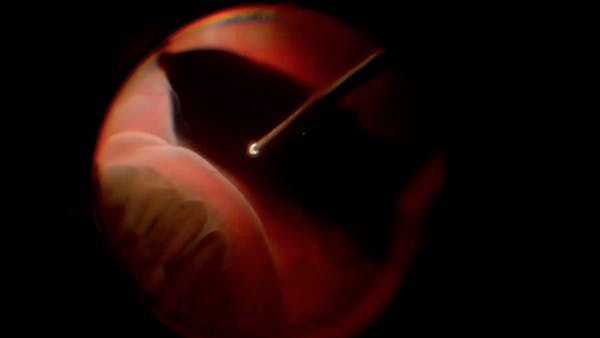

Yusuke Oshima, MD